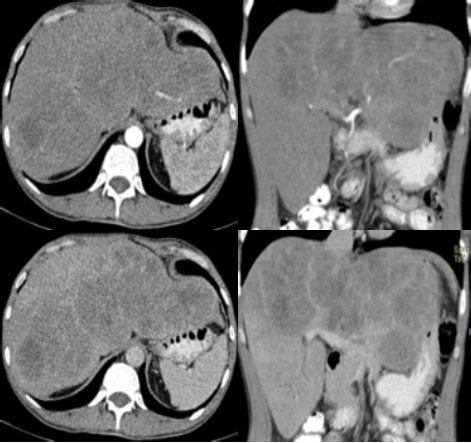

Ante hallazgos ultrasonograficos se decide realizar tomografia computarizada en la que se evidencian múltiples lesiones hepáticas hipodensas comprometiendo lóbulo hepático izquierdo con lesiones satélites hacia lóbulo derecho sin evidenciar lesión en otro órgano (Figura 2), por lo que es llevado a biopsia hepática por trucut por servicio de cirugía general.

Figura 2 Tomografía computarizada con contraste oral e IV evidenciando Hígado aumentado de tamaño, Con múltiples lesiones hipodensas que realzan en fase arterial, siendo la de mayor tamaño en LHI con múltiples lesiones satélites en LHD, se evidencia circulación nutricia y realce periférico en fase venosa con escaso lavado en fase portal.